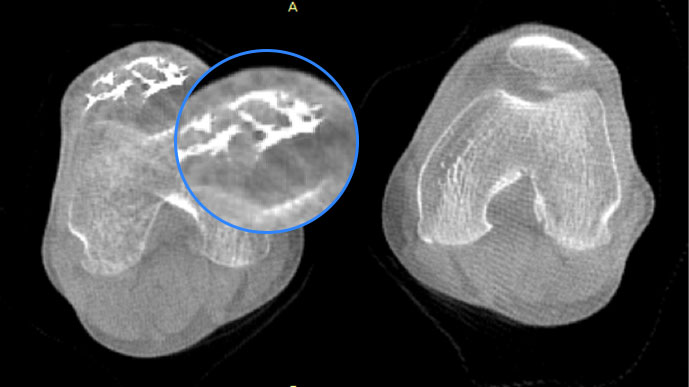

智能金属伪影抑制算法

关闭金属伪影校正

开启金属伪影校正